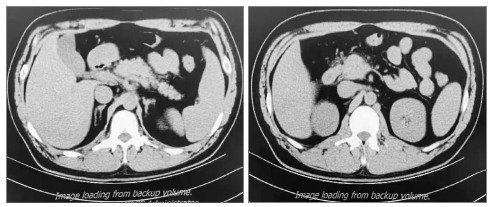

图 2图 3示:行血浆置换及CRRT治疗后,患者TG水平明显下降,腹痛也随之改善。患者于EICU共治疗4 d后一般情况显著改善,遂转入普通病区治疗。于入院第8日复查腹部CT可见胰周渗出较前吸收(见图 4),次日出院。出院后继续口服非诺贝特,3个月后随访查腹部CT可见患者胰腺体积、形态基本恢复,胰周渗出基本吸收,见图 5

左图为胰尾;右图为胰头 图 4 入院第8日上腹部CT